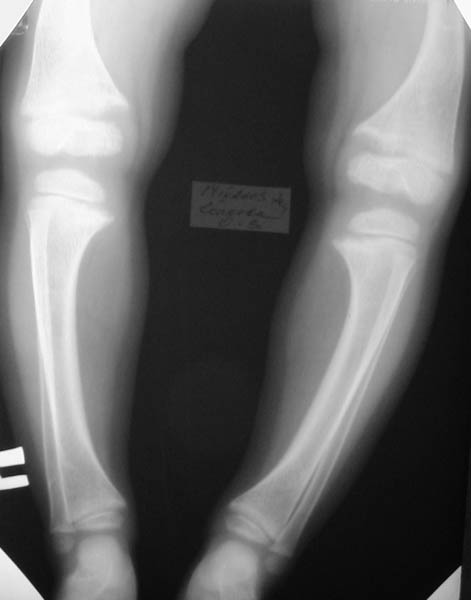

Таз Кисти Голени

Девочка, 3 года 11 мес. Дз: Фосфатдиабет (витамин Д-резистентный рахит).

Жалобы на задержку роста. Общие анализы крови и мочи без особенностей. Биохимический анализ крови: билирубин 7,7, АЛТ 0,30, общий белок 73, креатин 0,061, щелочная фосфотаза 49%мл/г, K+ 4,4, Na+ 139, Ca++ 0,93, Ca общий 2,5. УЗИ органов брюшной полости: норма, печень увеличена, паренхима однородна, сосудистый рисунок сохранен. Рентгенологический возраст 2 года, хронологический возраст 4 года. Ранее рекомендована ЛФК, витамины, видеин. Рекомендации по лечению? Заранее благодарен! С уважением, А.В.Владзимирский Донецкий НИИ травматологии и ортопедии